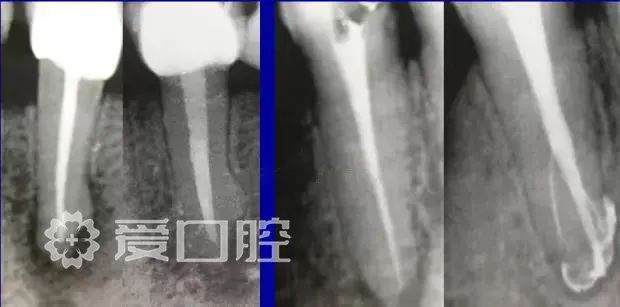

有些病例看上去似乎是完美的,但是患者就是感觉有明显的不适感,就应该考虑是否有未处理的根管内感染区域,分析是根管、峡部、分支、缝隙等原因后就要及时的采取措施。

失败病例的处理方法选择非手术再治疗还是手术再治疗,一般首选非手术再治疗,但要评估再治疗的预期结果,如(爱口腔)果非手术再治疗的对患牙的创伤太大或预期效果不确定就考虑手术再治疗,全面考虑分析后决定方法。要及时的决定下一步的处理方法,长期的反复的复诊观察是没有意义的,最后的结果是流失患者。

根管预备理想的情况应该预备到多大锥度,多少号,预备后根管空间是金字塔还是埃菲尔铁塔。专家经过离体牙根尖切片研究发现根尖狭窄部远比想象的要大,如果根管预备太小就会残留感染物,根管的部分空间就不会预备到,残留的感染物就会造成治疗效果达不到预期目标。只有做到了充分的预备,尽可能的多冲洗才会有好的结果。

根管治疗要做到看清楚,去干净,充恰满,封严密,就会达到期望的结果。2200年前的病例只充填了冠1/3可以理解、可以接受;今天我们有先进的设备和材料,就要充填出大锥度高密度的完美结果。理念决定技术,标准决定技术的提高和进步。